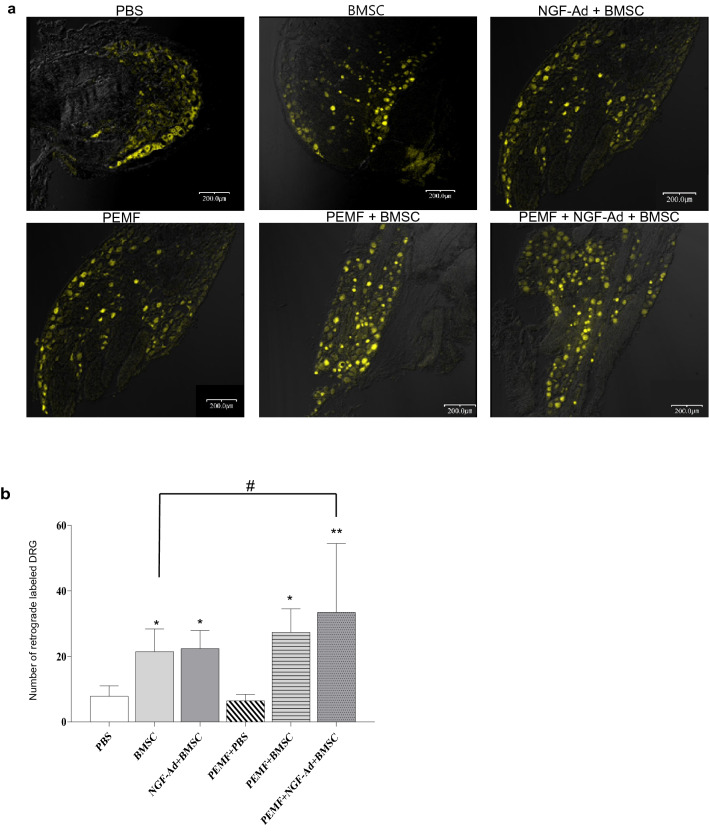

Retrograde tracing

The number of retrogradely labeled neurons was significantly higher in the BMSC, NGF-Ad + BMSC, PEMF + BMSC and PEMF + NGF-Ad + BMSC groups (BMSC = 21.46 ± 6.91, NGF-Ad + BMSC = 22.40 ± 5.49, PEMF + BMSC = 27.38 ± 7.12 and PEMF + NGF-Ad + BMSC = 33.44 ± 21.02) compared to the other two groups (PBS = 7.83 ± 3.14, PEMF + PBS = 6.43 ± 1.97). Transplantation of BMSCs was assumed to have accelerated neuronal regeneration. Among the four groups that contained cells, the PEMF + NGF-Ad + BMSC group showed a significantly higher number of retrogradely labeled neurons compared to the BMSC group (Fig. 4a, b).

Fig. 4.

Retrograde labeling of dorsal root ganglion (DRG). a Representative fluorescence photomicrographs of DRG showed fluorescent (yellow color) cell bodies of retrograde labeled with Fluorogold, 3 weeks following the crush injury. Scale bar 200 μm. b Mean count of retrograde labeled DRG. All groups BMSCs exhibited a significantly higher number of back-labeled DRG than both the control and PEMF group. Furthermore, among the groups that were injected with BMSCs, the co-treatment of NGF-Ad-infected BMSCs and PEMF demonstrated a significantly higher number of back-labeled DRG as compared to BMSCs alone. All values are presented as mean ± SD (∗ : p < 0.05 vs. Control and PEMF, ∗ ∗ : p < 0.0001 vs. Control and PEMF, #: p < 0.05 between two selected groups)